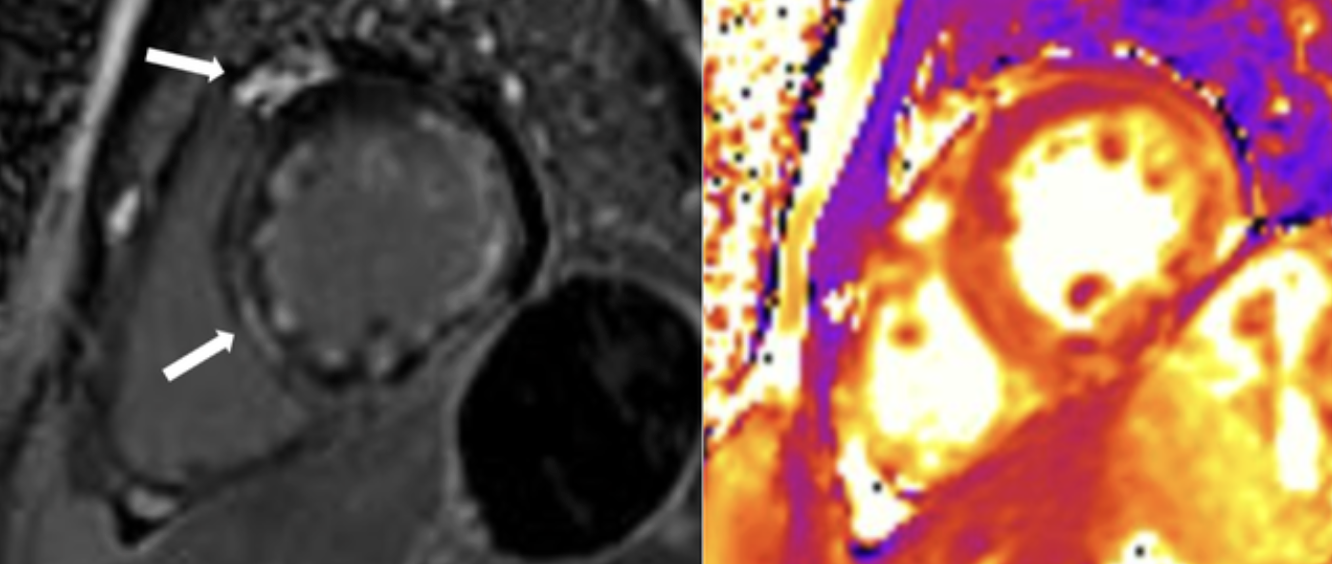

Hình cộng hưởng từ tim của anh L.V.H ghi nhận nhiều tính hiệu viêm cơ tim (Mũi tên màu trắng).

Kết quả chụp cộng hưởng từ tim sau đó ghi nhận tình trạng viêm cấp tính ở cơ tim và màng ngoài tim, phù hợp với chẩn đoán viêm cơ tim cấp.